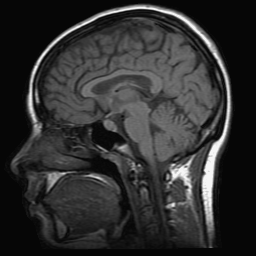

To simulate various input noise levels, several values for have been selected in the range . The set of high-quality magnitude MR test images used is shown in Fig. 6, and may be obtained from http://bigwww.epfl.ch/luisier/MRIdenoising/TestImages.zip.

V-C Denoising of a magnitude MR knee image

We have also applied our CURE-LET denoising algorithms to an actual magnitude MR image of the knee. This 16-bit raw image has been acquired on a Siemens 1.5 Tesla Magnetom Sonata MR system, following a sagittal T2-weighted protocol. The standard deviation of the complex Gaussian noise has been estimated from a signal-free region of the squared data, as , and subsequently treated as known.

Fig. 11 shows the denoising results of the various CURE-LET algorithms. As observed, the noise is efficiently attenuated and the contrast is significantly improved, owing to a proper reduction of the signal-dependent bias introduced by the noise.